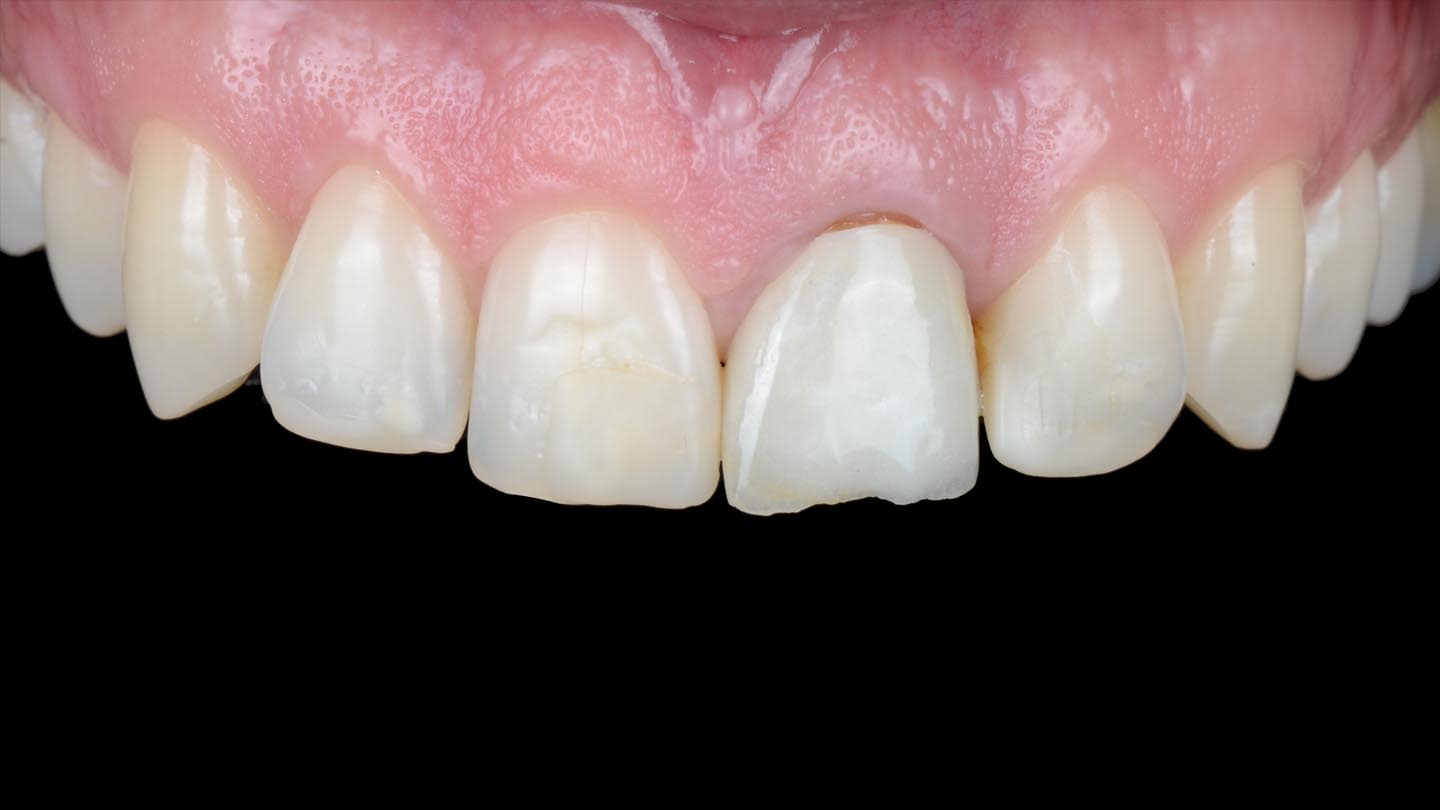

A 40-year-old male patient presented to the author’s (MR) office with the request to improve the esthetics of his smile, as there were several extensive infiltrated composite restorations and a chipped crown showing a severe dark color on an endodontically treated tooth (Figure 1 and Figure 2).

Following a comprehensive clinical, radiographic, and initial photographic assessment, ceramic restorations were chosen to restore function and esthetics. Given that the underlying structure of tooth No. 9 was presented with a fractured crown, a metal cast post, and dark discoloration, it was decided to fabricate a crown with an opaque core using high-opacity LDS ceramic along with a bonded lithium-disilicate veneer on top to enhance the esthetic outcome. For teeth Nos. 7, 8, and 10, LDS ceramic veneers were chosen.